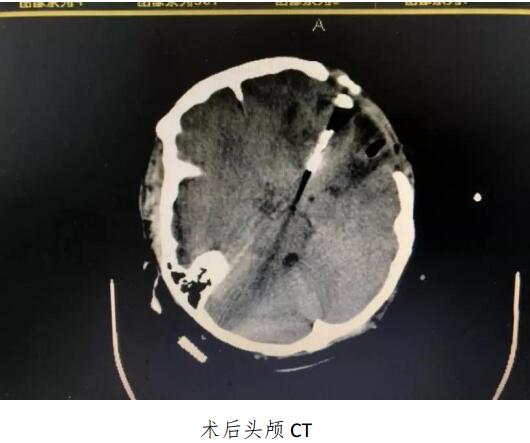

男同视频 成功开展颅内动脉瘤夹闭术及脑血管造影动脉瘤栓塞术